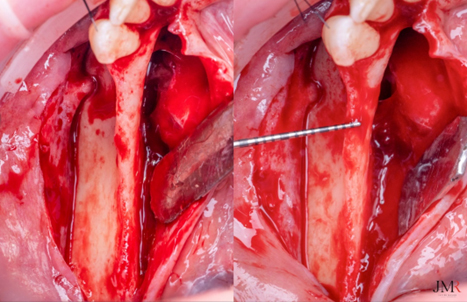

Figura 4.

Visión lateral del defecto óseo, donde se observa la salida del nervio mentoniano y su relación con la zona que vamos a regenerar.

Figura 5.

Realizamos unas perforaciones corticales sobre el defecto, para promover la vascularización y la osteogénesis en el injerto óseo.